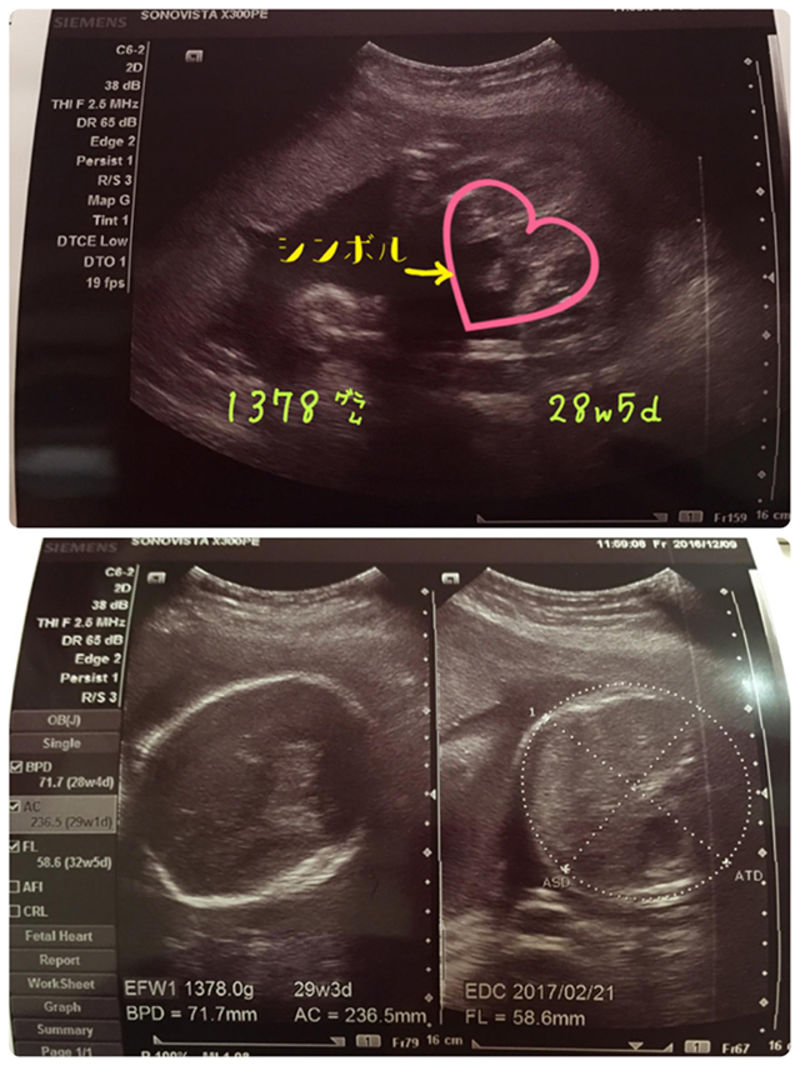

赤ちゃん28w5d

エコー写真から性別判定お願いします 妊娠28週です 担当の先生には男

赤ちゃんがお腹の中にいることが分かると、とても幸せな気持ちになますね。 妊娠が発覚して、まず何が気になるって…赤ちゃんの性別です!! うちのパパは女の子希望でしたので、ずっとエコー写真を見ては 「これは女の.. 女の子エコー写真股 — エコー検査で、赤ちゃんの性別が判明するのはいつごろなのでしょうか。写真の見分け方や男の子、女の子それぞれの見え方の特徴を画像付きで解説します。男の子はピーナツ状の突起物、女の子は木の葉やコーヒー豆が股間に見えますが、ときには判定間違いも起こり .. エコー写真から性別判定お願いします 妊娠28週です 担当の先生には男 こちらの記事に対するkozokaeruさんのコメントです 胎児 エコー 女の子 割れ目女の子 エコー 木の葉 写真女の子 エコー 突起物 画像エコー写真 男の子 女の子 違..